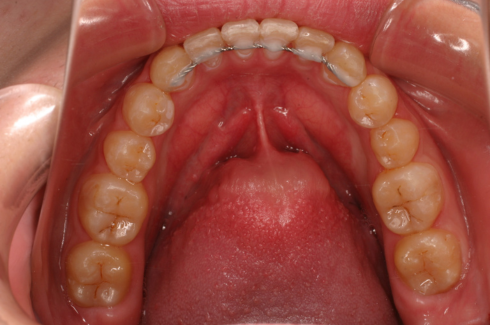

2期治療では、永久歯列完成頃に歯並び咬み合わせ全体の治療を行います。

12~14歳頃(顎の成長に問題が無い時点)から、本格的な歯列全体の治療を行っていきます。

歯を動かすためにワイヤーの力を利用して歯の移動を行う装置を、マルチブラケットアプライアンスと呼びます。

セルフライゲーションブラケット装置(デーモンクリア)、歯の裏側に装着するカスタムメイド型リンガルブラケット等の種類があります。